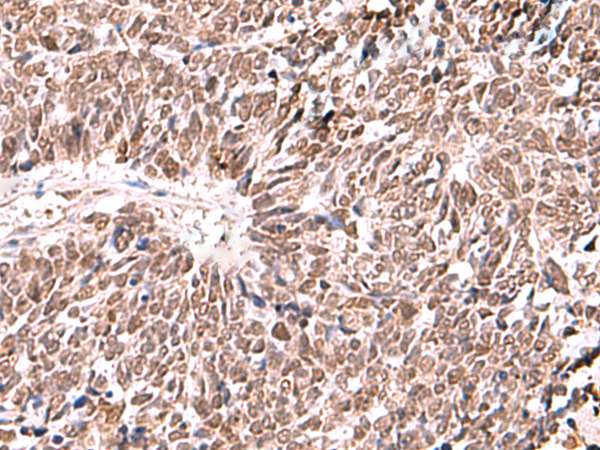

分类: 科研抗体货号: P10166别名: dJ283E3.1应用: IHC反应种属: Human, Mouse